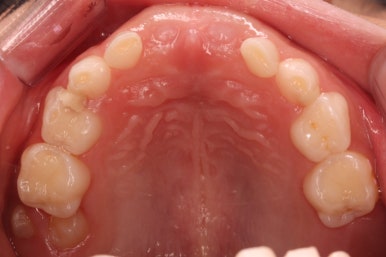

부산어린이치아교정 키다리아저씨치과에 처음 내원하셨을 당시의 입안의 모습입니다. 네 군데 모두 어금니는 보이지 않습니다.

입 안에서 문제점이 발견되지 않는 경우 일이 커지는 경우가 많은데 이번 환자분은 X-ray를 찍어봄으로써 문제를 조기에 발견하고 치료를 할 수 있었습니다.

어금니를 개선해 주는 치료만 해주면 되는 경우였고, 현재 입 안에서 해당 어금니가 일부라도 보이지 않기 때문에 여러 가지 치료옵션을 염두에 두고 몇 달 간격으로 체크해 보기로 하였습니다.